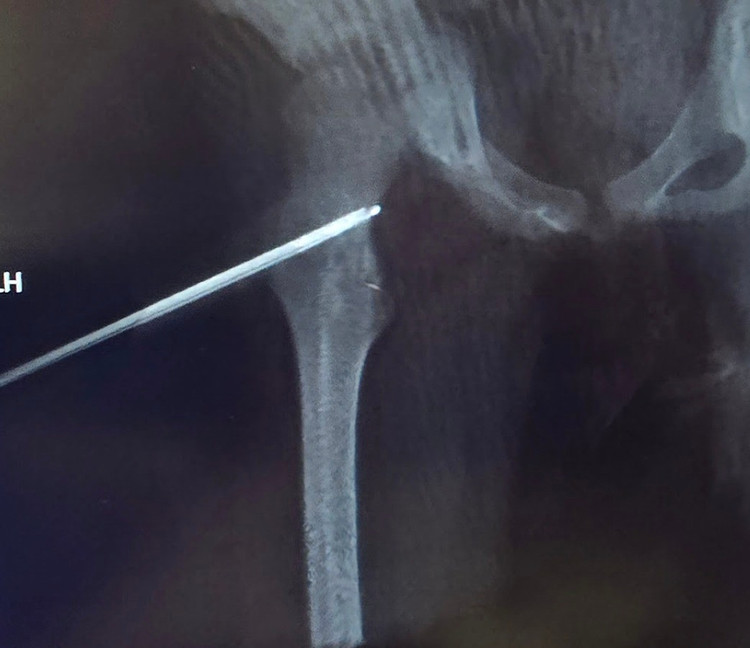

Can thiệp tiến hành bằng mê nội khí quản, khoan xương qua cổ xương đùi để vào đến khối u xương dưới định vị bằng Siêu âm, Fluoscopy và Conbeam CT. Đốt sóng cao tần bằng kim có đầu đốt dài 0,7 cm.

Ca can thiệp diễn ra thành công trong khoảng 30 phút. Ngay sau can thiệp, bé gái chỉ cần một liều thuốc giảm đau duy nhất, và hôm sau đã có thể ra viện.

Quan trọng hơn, những cơn đau đã hoàn toàn biến mất. Người mẹ xúc động chia sẻ trong nước mắt: "Cảm ơn các bác sĩ, sau 6 tháng, cháu đã có một giấc ngủ yên bình đầu tiên mà không bị đánh thức bởi cơn đau".